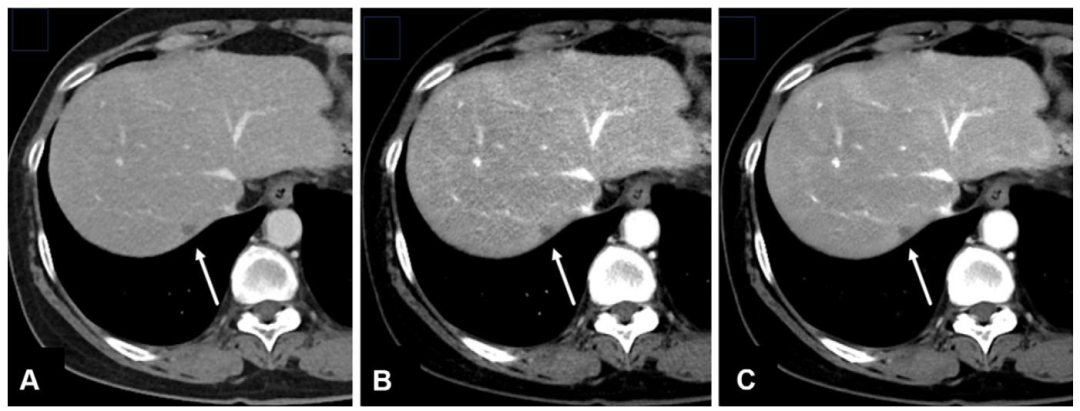

轴位增强 CT 图像显示肝被膜后方的微小转移瘤(A 图箭头所示)。初始采用三维自适应迭代剂量降低技术(AIDR 3D;佳能医疗系统)重建的图像噪声明显(A 图);经 AiCE 重建后,信噪比(SNR)和对比噪声比(CNR)显著改善(B 图);采用新型 PIQE 算法后,图像质量进一步提升,能更清晰地显示病变特征(如外壁增厚,C 图);必要时可将图像矩阵从 512 提升至 1024 以提高空间分辨率,结合 PIQE 算法可实现更优成像效果(D 图)。